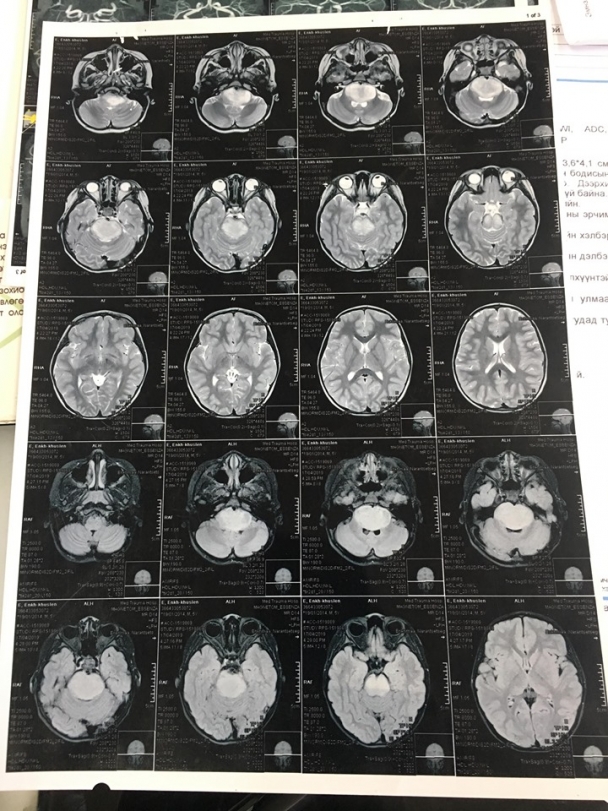

Э.Энхмарад охины ээж Н.Оюунтуяа хэлэхдээ " Охин минь 5 настай. Өмнө нь эрүүл саруул, сэргэлэн цовоо охин байсан. Энэ жилийн гуравдугаар сарын эхээр өвчин нь илэрч эхэлсэн. Юм ярихад ойлгохгүй болж, шүлс нь гоожоод л, нэг талын хөл нь хазайх зэрэг шинж тэмдэг илэрсэн. Эхлээд бид сэтгэцийн эмчид үзүүлэхэд сэтгэц биш гэсэн. Дараа нь ЭХЭМҮТ-ийн мэдрэлийн эмч н.Туулд үзүүлэхэд нэг талаараа тархины хавдар эсвэл саажилт явагдаж байна гэсэн. Ингээд MRI зураг авахуулахад тархины хавдар байсан.

Хавдар дундаа 1000-д нэг тохиолддог хүний уртавтар тархинд байдаг мэдрэлийн судас дарсан хорт хавдар байсан.